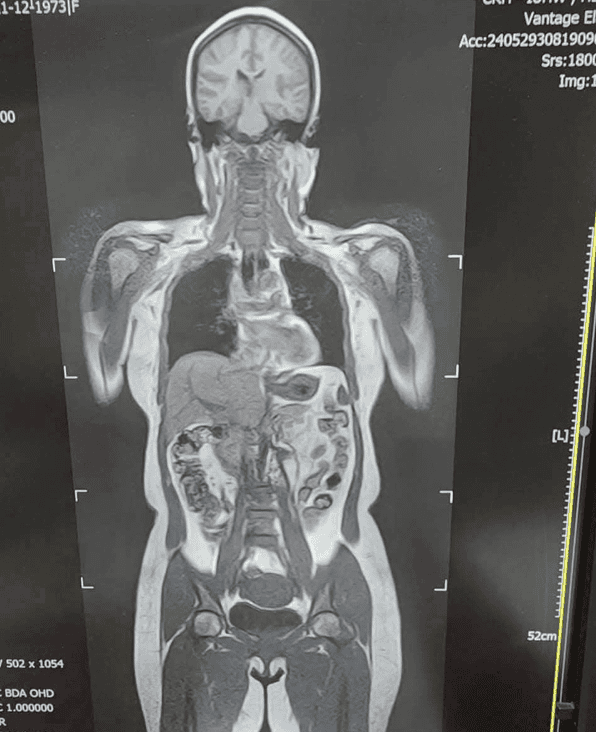

MRI DWIBS (Diffusion-weighted Whole Body Imaging with Background Suppression) là kỹ thuật chụp cộng hưởng từ khuếch tán toàn thân xóa nền, cho phép tầm soát toàn bộ cơ thể trong một lần chụp. Phương pháp này được ứng dụng hiệu quả trong tầm soát ung thư, phát hiện di căn và theo dõi tiến triển bệnh. So với các phương pháp chẩn đoán hình ảnh khác, MRI DWIBS sở hữu nhiều ưu điểm như: không nhiễm xạ, không cần tiêm thuốc cản quang, thời gian chụp toàn thân rất kỹ từ 50đến60 phút, người bệnh có thể sinh hoạt bình thường ngay sau khi thực hiện và phù hợp với cả người mắc bệnh đái tháo đường. Tuy nhiên, một số trường hợp không được chỉ định chụp MRI DWIBS, bao gồm người đang mang máy tạo nhịp tim, có mảnh đạn, mảnh kim loại gần mạch máu lớn hoặc các cấu trúc nguy hiểm, các dụng cụ cấy ghép trong cơ thể… Những trường hợp này cần thông báo đầy đủ với bác sĩ trước khi thực hiện chụp chiếu.